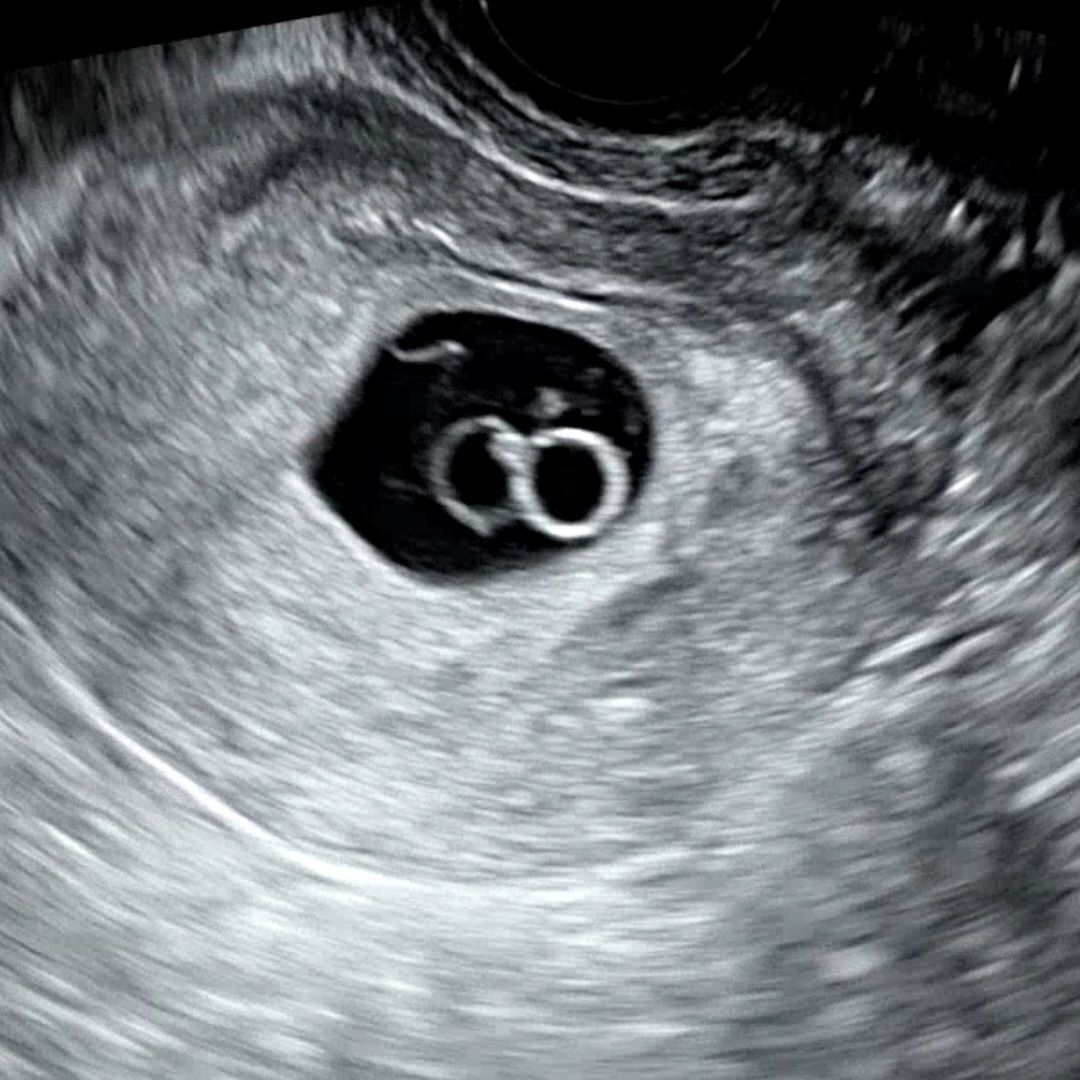

시험관으로 배아 2개 이식해서 이란성 쌍둥이 임신 성공했습니다! 그런데.. 오늘 7주 4일차에 갈색냉이 있어서 불안한 마음에 병원진료 보고왔는데 초음파를 보시더니 첫번째 아기집에 난황으로 보이는 '아기였던 것 일수도 있는' 구조물이 있다고 하시고.. 경과를 지켜보자고 하셨거든요... 움직임이 있거나 심장박동이 보였으면 아기가 또 있네요 하셨을건데.. 그렇게 말하셨다면.. 아닌걸까요?ㅠㅠㅠ 세쌍둥이는 무섭고 겁이나서, 진짜 아기가 한명 더 찾아왔다면 축복이지만.. 7주차에 이렇게 쌍둥이가 (한명더ㅠㅠ)발견되는 경우도 있나요..? 다른 두명 아기는 심장소리 잘 들리고 손발 살짝 보이는 정도로 잘 자라고는 있습니다..!